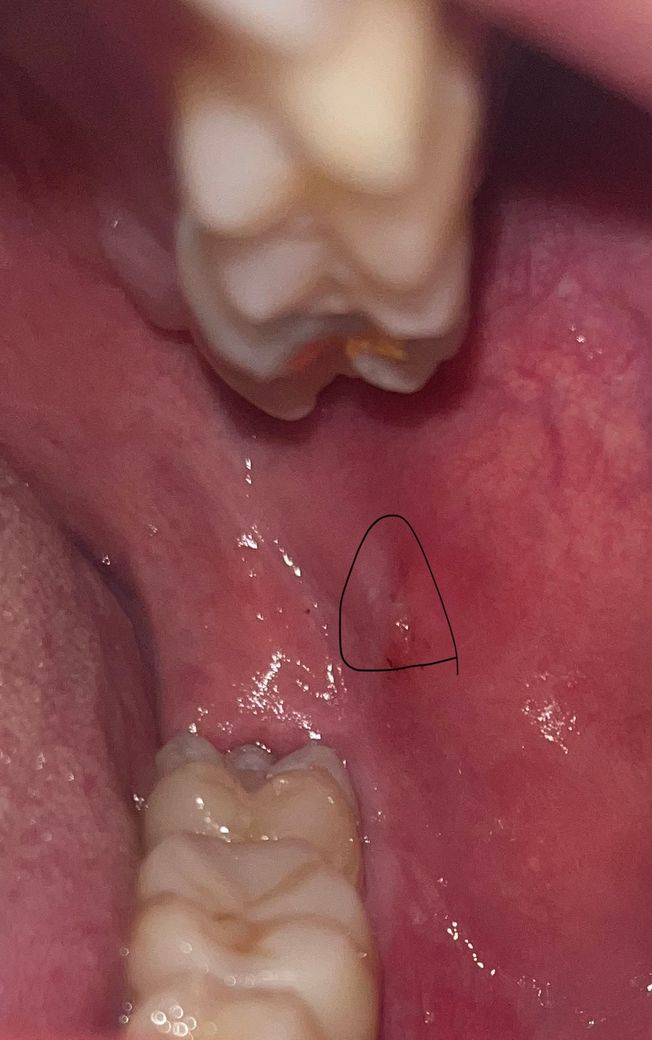

갑자기 구강암 관련 유튜브 영상을 보다가 무서워져서 질문드립니다왼쪽 어금니사이 볼쪽에 뭔가 물집같이 잡힌게있는데 이게 아프지않고 에전부터 있었던거같습니다 구내염인지 자주 이빨에 씹혀서 뭉친건지 설마 구강암인지 갑자기 무서워져서 질문드려요ㅠㅜ 답변 부탁드립니다흡연음주 다하고 나이는 이십대 중후반입니다

구강암은 아닙니다. 저부분은 위아래 치아에 볼살이 씹혀서 생긴 자국인거 같습니다. 걱정하지 않으셔도 됩니다.

해당부위의 병소 모양은 볼 씹음에 의한 외상성소포로 치유과정 내에 있는 것으로 보입니다.

2주 이내에 해당 병소가 사라지시면 아무 이상 없는거고.

2주 이내에 해당 병소가 사라지지 않으시면 구강외과를 내원하셔서 조직검사를 받아보시기 바랍니다.

사진으로 봤을 때는 정확하게 확인하긴 힘들지만 구내염처럼 보입니다 대부분의 구내염은 일주일에서 2주일 사이 없어지기 때문에 몸에 컨디션을 좋게 유지한다면 금방 회복될 수 있습니다 2주 이상 지속되는 현상이 있다면 치과에서 자세한 진료를 받아 보는 것이 좋습니다

구강 내 백색병소의 경우 그 자체가 악성병소가 아닐지라도 악성전환이 가능한 전암병소일 수 있고 이런건 사실 사진상으로만 봐서는 진단이 불가능합니다 대학병원치과 내과에서 생검을 받아보시는게 좋겠습니다

구강암 아니니 걱정 안해도 됩니다. 단순한 염증으로 보입니다. 시간이 지나면 없어질 것을 보입니다.